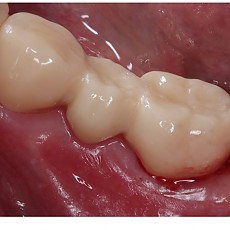

시술전후사진 12 페이지

Total 189건 12 페이지